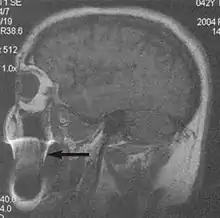

Flow can manifest as either an altered intravascular signal (flow enhancement or flow-related signal loss), or as flow-related artifacts (ghost images or spatial misregistration). Flow enhancement, also known as inflow effect, is caused by fully magnetised protons entering the imaged slice while the stationary protons have not fully regained their magnetization.[1]

The fully magnetized protons yield a high signal in comparison with the rest of the surroundings. High velocity flow causes the protons entering the image to be removed from it by the time the 180-degree pulse is administered. The effect is that these protons do not contribute to the echo and are registered as a signal void or flow-related signal loss (Fig. 2).[1]